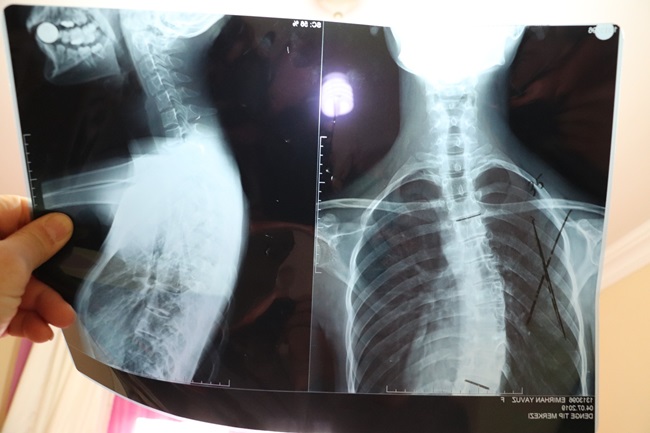

Zonguldak’ın Ereğli ilçesinde yaşayan 19 yaşındaki Otizmli Emirhan Yavuz, skolyoz hastalığı ameliyat edilemediği takdirde hayatını kaybetmekle karşı karşıya. Anne Eda Tok, tek başına bakmaya çalıştığı oğlunu kurtarmak için hayırseverlerden yardım bekliyor.

Kısa süreye kadar İstanbul’da yaşayan ve eşinden boşanması üzerine memleketi Ereğli’ye yerleşen Eda Tok, otizmli olan 19 yaşında ki skolyoz rahatsızlığı oğlunu tedavi ettirmek için yardım bekliyor. Bugüne kadar birçok Devlet Hastanesine giden ancak burada oğlunun ameliyatı için çözüm arayan anne Eda Tok, gittiği her hastaneden eli boş döndüğünü söyledi. Özel hastanelere de gittiğini ancak özel hastanelerde de yaklaşık 50 bin liralık bir maliyet kendisine çıkarıldığını kaydeden anne Eda Tok, imkânsızlıklardan dolayı ameliyatı gerçekleştiremediklerini kaydetti.

Skolyoz hastalığından dolayı iç organların da zarar görmeye başladığını ve kısa zaman da ameliyat olmaması durumunda oğlunun hayatını kaybedeceğini ifade eden anne Eda Tok “Çocuğum Otizm hastası. 10 yaşından bu yana çekiyoruz. İstanbul ilinde birçok hastanede gösterdik. Ama ameliyat olmayacağını söylediler. Ailevi nedenlerden dolayı Ereğli’ye geldik. Buradaki hastanelere de gittik. Onlarda aynı cevabı verdiler. Özel hastaneye gönderdiler. Özel hastanelerde de maddi durumdan dolayı ameliyat yaptıramadık. Doktorlar bir an önce ameliyat olmazsa oğlumun hayatını kaybedeceğini söylediler. Ben yardımseverlerden devlet büyüklerimden bana destek vermelerini ve yardım etmelerini istiyorum. Oğlumu kaybetmek istemiyorum” dedi.